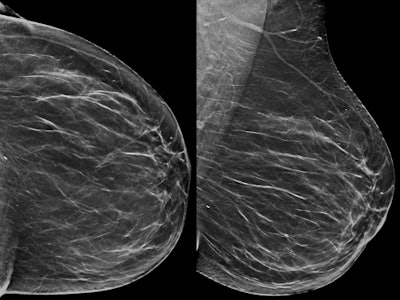

An example of architectural distortion detectable only on DBT. Above: A 54-year-old woman with no abnormality on synthesized 2D mammography. Below: Architectural distortion depicted on the left tomosynthesis (upper-outer quadrant) image. The microhistological examination after DBT-guided, vacuum-assisted biopsy revealed an invasive ductal carcinoma (grade 2), confirmed by surgical excision. All images courtesy of Dr. Francesca Caumo."The transition to DBT plus synthetic 2D imaging in the Verona screening program was associated with increased breast cancer detection rates compared with screening with FFDM, with comparable recall rates for these screening strategies," the study authors wrote (Radiology, 13 December 2017).